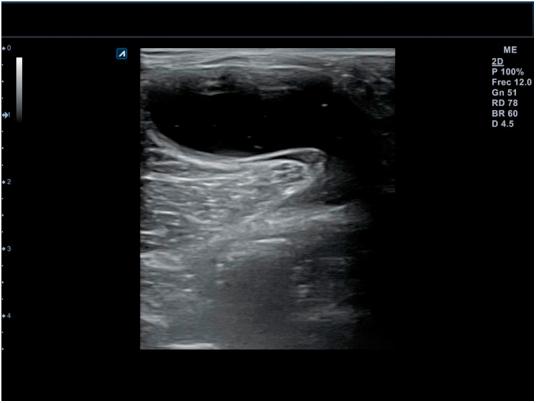

Musculoskeletal ultrasound (MSU) is a technique which has been extended to practically all medical specialties that comprise this pathology. Family Doctor (FD) has not been away from this process due to its great wide of competences, using it in different scenarios inside his common practice in which he can get profits in a reliable, efficient and effective way. Ultrasound equipment incorporation in Primary Care (PC) centers is an increasing reality, contributing to high ranges of accessibility, immediacy and clinic handle capability, and thus, together with the high prevalence in this area in locomotor apparatus, turns MSU into an strategic action for the improvement of the resolving capacity and consequently for the health care. To ensure proficiency among users, it's being necessary to define the benefits and potential risks its use can cause, as well as its different scenarios, avoiding unnecessary explorations and optimizing the investment of this resource at PC level. This paper pretends to summarize the state of the art of the musculoskeletal ultrasound and its benefits for the FD into this efficient and effective scenarios.

肌肉骨骼超声(MSU)是一种已被应用于几乎所有涉及该病理学的医学专业的技术。家庭医生(FD)因其广泛的能力范围也参与到了这一进程中,在其日常诊疗的不同场景中使用该技术,从而能够以可靠、高效且有效的方式从中获益。超声设备在基层医疗(PC)中心的应用日益普遍,这有助于提高可及性、即时性和临床处理能力,因此,鉴于运动系统在该领域的高患病率,肌肉骨骼超声成为提高诊断能力进而改善医疗保健的一项战略举措。为确保使用者的专业水平,有必要明确其使用可能带来的益处和潜在风险,以及不同的应用场景,避免不必要的检查,并在基层医疗层面优化该资源的投入。本文旨在总结肌肉骨骼超声的现状及其在这些高效有效场景中为家庭医生带来的益处。